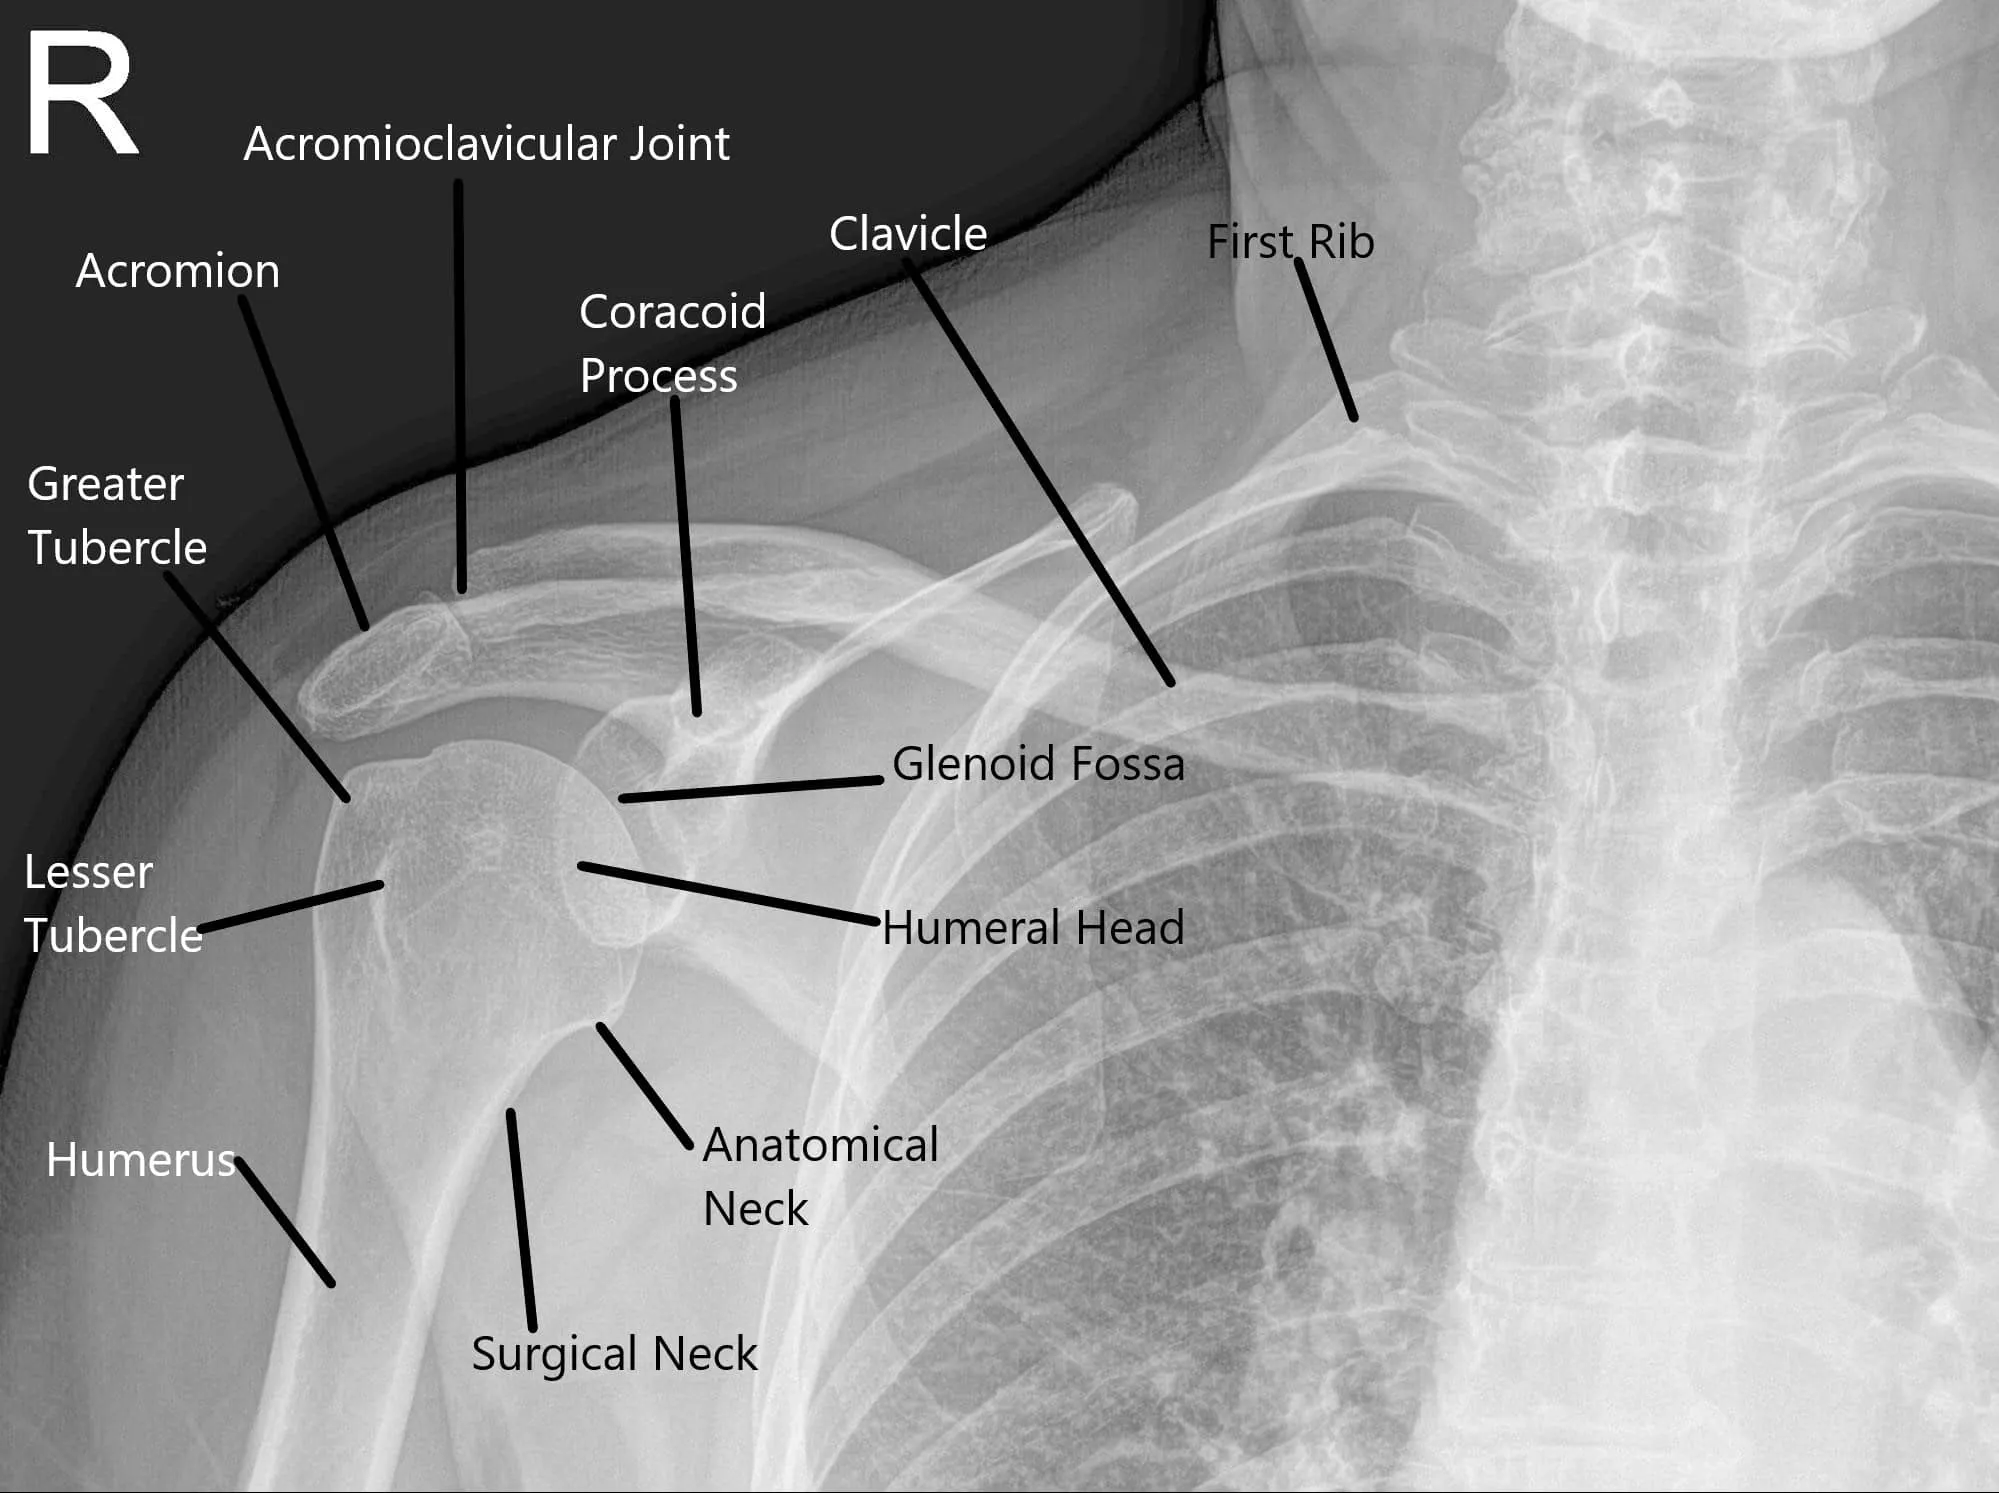

Radiografía que muestra la anatomía normal del hombro.

¿Cómo funciona normalmente una parte del cuerpo? (Anatomía relevante)

La articulación del hombro está formada por el húmero (hueso de la parte superior del brazo), la escápula (omóplato) y la clavícula (clavícula). La bola del húmero encaja en la cavidad poco profunda de la escápula, formando una articulación esférica. Esta configuración proporciona una gran amplitud de movimiento. Los ligamentos, tendones (como el manguito de los rotadores) y el labrum estabilizan y sostienen la articulación, permitiendo un movimiento suave y flexible.